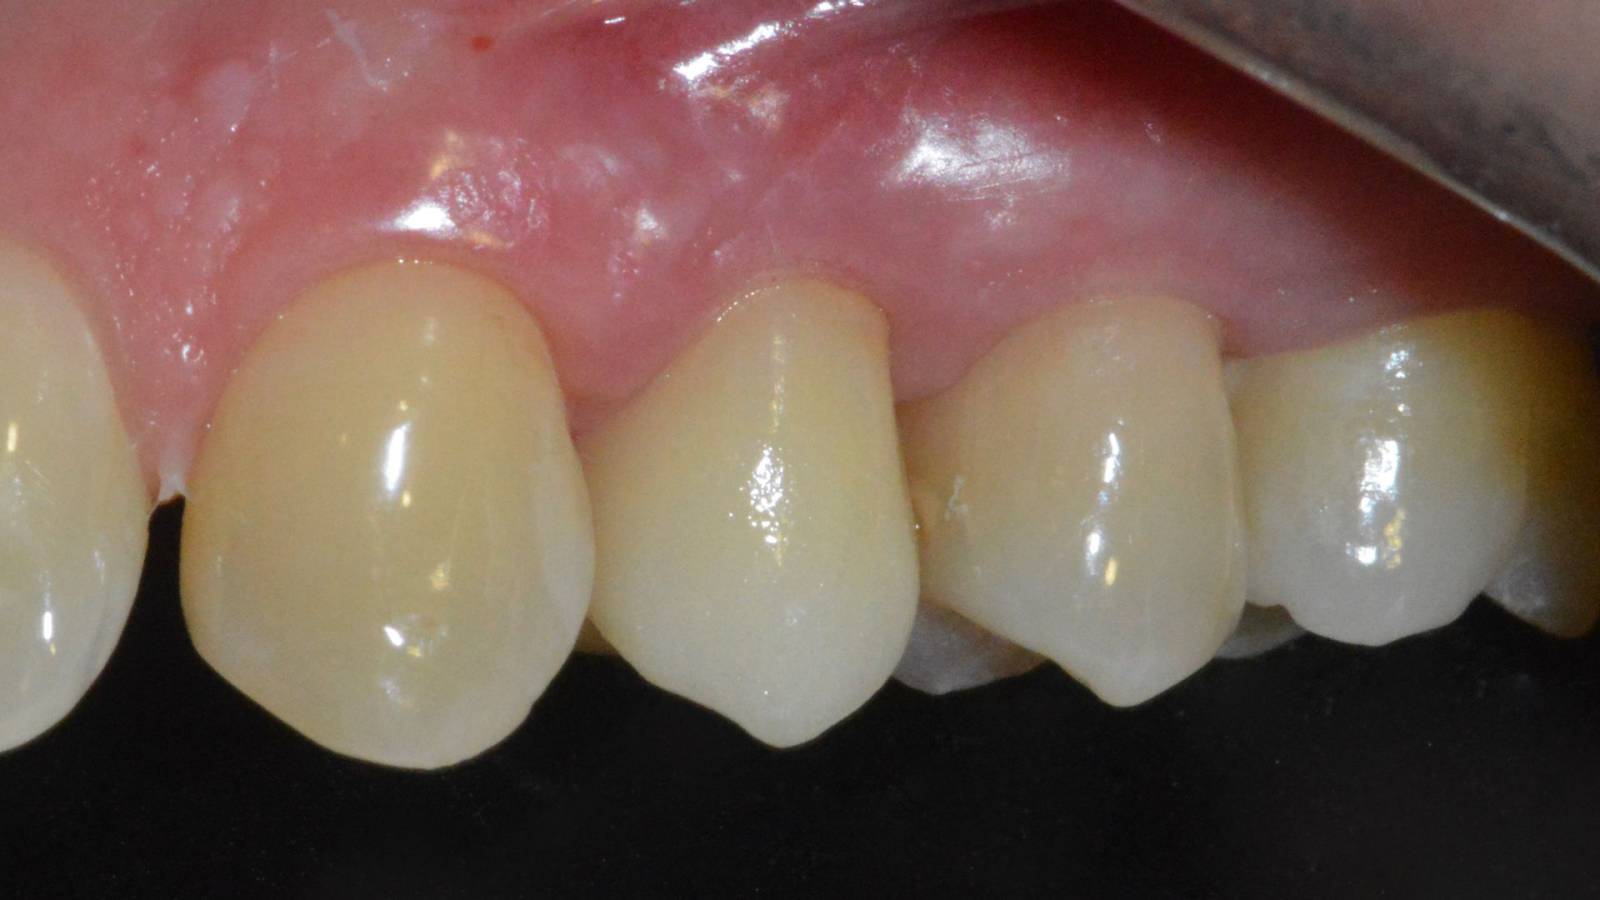

Before

Inadequate fillings on teeth 12-22, an uneven gingival line on 12 and 11 and incisal edges severely eroded.

After

Four highly esthetic and individualized lithium disilicate ceramic crowns.